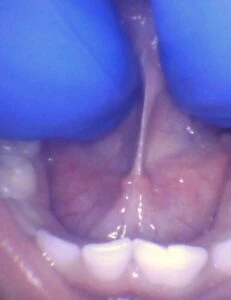

IMAGES OF TONGUE- AND LIP-TIES

Posterior tongue-tie in a child seen with lifting the tongue. The posterior or “hidden”tongue-tie can cause the same symptoms including nursing pain and poor weight gain, as a to-the-tip tie in a child